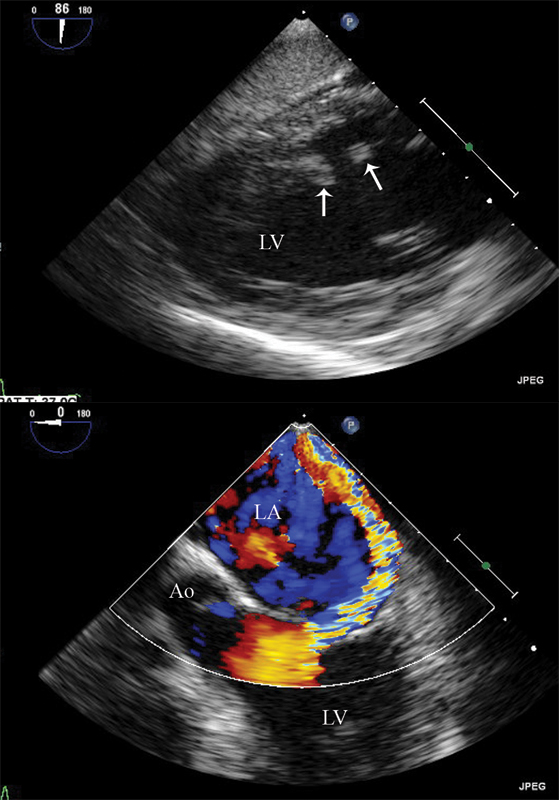

فحوصات تشخيصية لبعض امراض القلب والشرايين التاجية